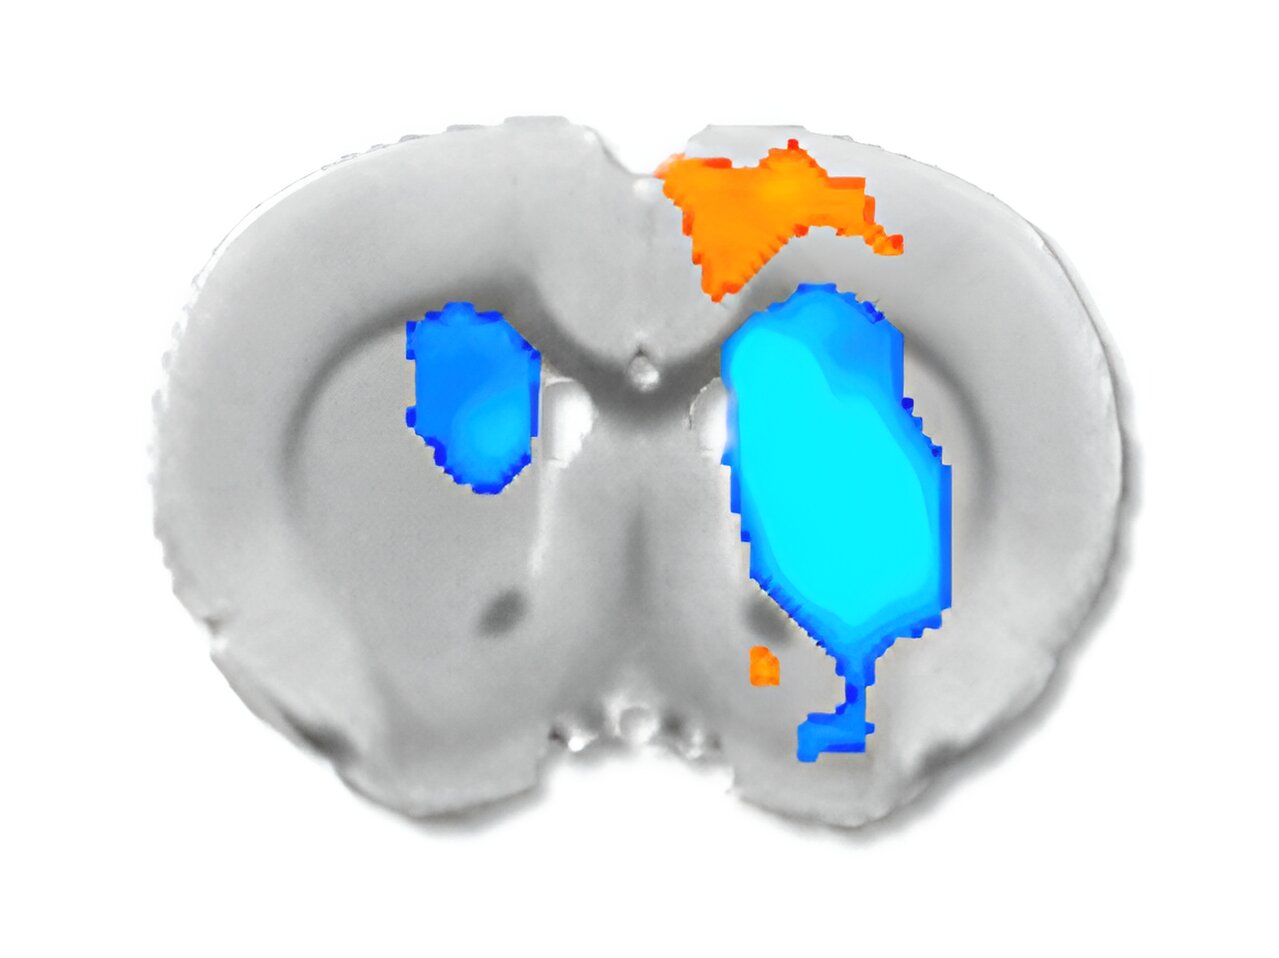

An fMRI indirectly measures this electrical activity by detecting changes in oxygen levels in the blood. This is called the blood-oxygen-level-dependent (BOLD) response.

This activity is color-coded in the resulting fMRI images.

These activities are color-coded on the brain images, allowing the doctor to see a map of your brain activity.